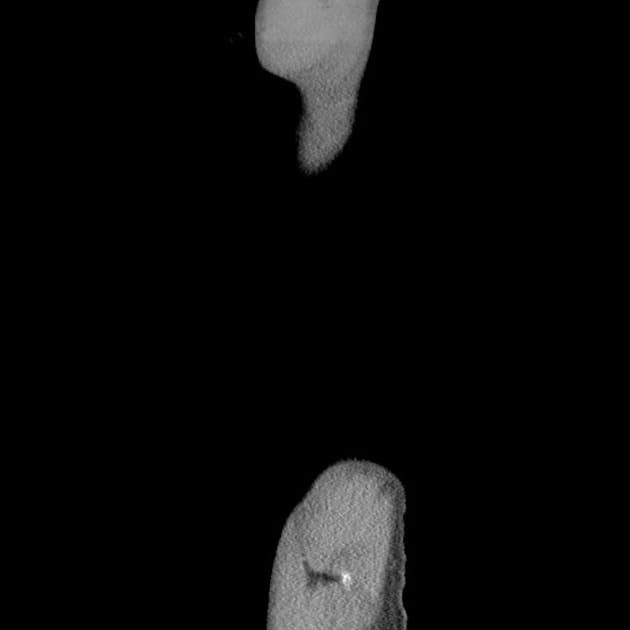

Axial C+ portal venous phase

CT•Axial C+ portal venous phase•1 / 497

dày thành đồng tâm vùng trực tràng - đại tràng sigma, kèm thâm nhiễm mỡ nhẹ xung quanh. mất hoàn toàn các nếp gấp đại tràng (dấu hiệu ống chì) ở đại tràng sigma. ít dịch tự do trong vùng chậu. còn ống phúc tinh mạc chứa dịch ổ bụng. THẢO LUẬN: Dày thành đồng tâm vùng trực tràng - đại tràng sigma kèm theo mất các nếp gấp đại tràng gợi ý bệnh lý viêm loét đại tràng.